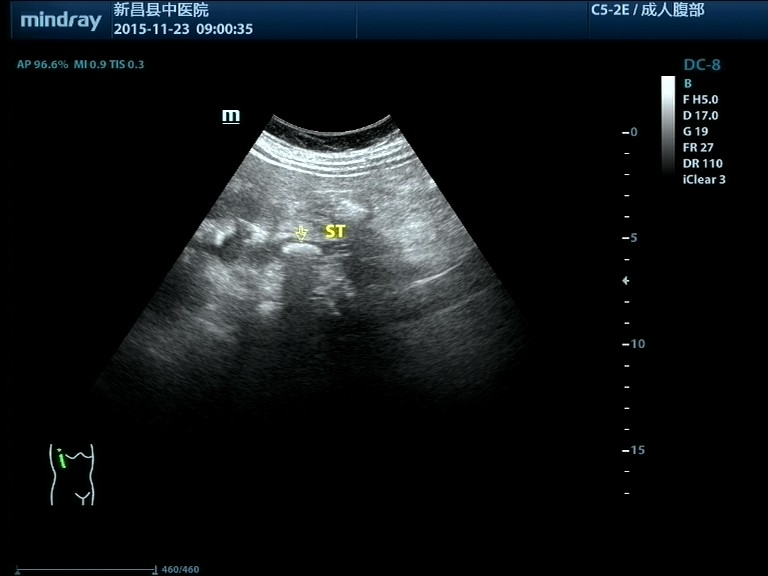

泌尿系结石

夏季到了,急诊室内面色苍白,捂着肚子,额头沁满汗珠的患者越来越多了,见到医生的第一句就是“医生,我的结石又痛了!” 泌尿系结石是一种常见病,多发病,医学上把肾脏结石、输尿管结石、膀胱结石和尿道结石统称为尿路结石。男性发病率明显高于女性。 01 尿路结石常见的病因 1.个体因素和遗传因素。 2.长期在高温环境中工作,机体水份蒸发多,尿液浓缩,容易形成结石。 3.代谢性疾病,如甲状旁腺功能亢进,尿中钙盐增多;痛风病人尿中尿酸盐增加,均易得结石。 4.某些食物或药物的长期作用使尿液酸碱度改变,也是结石生成的一种诱因。 5.前列腺增生或其他原因引起的排尿不畅,慢性尿潴留,因尿液浓缩尿液中盐份容易沉积,形成结石。 6.长期卧床,因骨质脱钙,血钙浓度增加易致结石形成。 结石的诱发因素多种多样,因此结石的预防也要有针对性。结石成分的分析有助于明确病因。盲目忌口对预防结石收效不明显。这里顺带一句,很多病人误认为柿子吃多了会得尿路结石,实际上这是一种讹传,柿子吃多了可能会凝结成胃肠道柿石,而与泌尿系结石完全没有关系。 02 泌尿系结石发作时的症状和体征 泌尿系结石原发部位一般都在肾脏内,平时不会有什么感觉,只有等结石掉入到肾盂出口处或输尿管内,引起输尿管梗阻和痉挛时才会出现一系列症状和体征。输尿管结石常停留于上端、下端及髂血管旁三个生理性狭窄处,结石对管壁的摩擦和刺激,可导致输尿管局部粘膜损伤、水肿甚至并发炎症。 结石疼痛常常呈突发性,表现为一侧腰部或腹部刀绞样疼痛,多数疼痛剧烈难忍,部分病人疼痛可放射至腹股沟区或会阴部。可伴有恶心呕吐、血尿,尿频、尿急、尿痛及反射性少尿。 体征表现为面色苍白,痛苦病容以及腰痛特有的姿势,检查可有肾区叩击痛。少数输尿管结石病人可以长期没有明显症状,往往要等到健康检查时才发现。 泌尿系结石的诊断:泌尿系统结石诊断并不难,一般通过超声或CT检查就能明确结石的大小和部位,肾输尿管有无扩张、积水。尿检有无红细胞可作为参考依据。 肾结石 肾积水 输尿管结石 膀胱结石 03 泌尿系统结石的治疗 1. 肾脏结石比较大的,或数量较多的,或伴有积水的可考虑外科微创或手术治疗。肾结石较小的一般没有症状也不影响肾脏功能,可不作处理。 2.输尿管结石不管在哪个部位,基本上都有不同程度的输尿管扩张和肾脏积水,时间久了积水可能会加重,影响肾脏功能。因此输尿管结石一经确诊一定要尽早治疗。0.5--0.6cm及以下的结石如果疼痛不是很厉害可以选择药物排石,但切记要间隔一星期左右复查,直到结石排出。较大的结石或保守治疗不能排出的结石可首先考虑体外冲击波碎石治疗。 3.膀胱结石最大径在3cm以下且前列腺增生不明显的可考虑体外碎石治疗。结石过大,或前列腺增生显著的可选择钬激光治疗或膀胱切开取石。 泌尿系结石虽然不算什么大病,但发作时疼痛是最剧烈的,大多需要急诊处理。体外冲击波碎石具有简便快捷,疗效确切,安全性高、痛苦较小、费用合理等优势,病人普遍容易接受,可以作为治疗泌尿系结石的首选。少数病人碎石后结石仍无法排出,或者是结石被包裹的病人则需要泌尿外科进一步处理。 输尿管结石碎石后呈长条状 敲黑板啦——预防结石有妙招●● 1.养成多饮水的习惯。多饮水可稀释尿液,降低尿内各种盐类的浓度。水源的改善对结石的预防也有一定的意义。 2.尽早除去尿路梗阻因素,如前列腺增生症、尿道狭窄等。 3.积极、规范、彻底治疗泌尿系的感染性疾病。 4.长期卧床的病人,应鼓励多活动,勤翻身,减少骨质脱钙。 5.有甲状旁腺机能亢进者,应积极治疗。